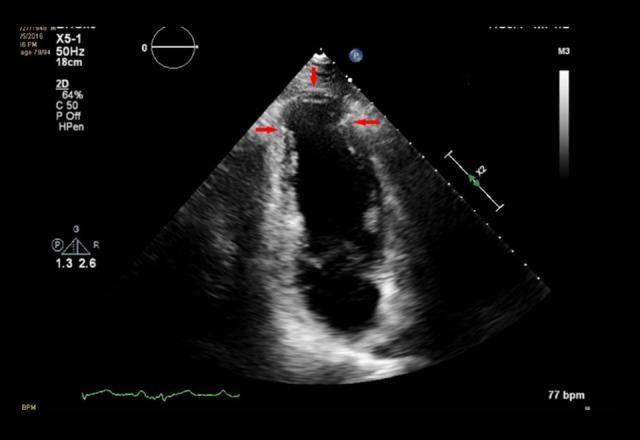

BACKGROUND Electrocardiographic presentations of left ventricle aneurysms are diverse; however, a persistent ST segment elevation post myocardial infarction is most commonly reported. CASE REPORT The authors present a case of a 67-year-old man who presented to the emergency department after three days of chest pain and was found to have an acute myocardial infarction with an incidental finding of a left ventricular aneurysm. His surface electrocardiogram, however, demonstrated only inverted T waves in the precordial leads. He had a very elevated serum troponin I consistent with an acute myocardial injury which prompted a cardiac catheterization with angioplasty. Post angioplasty, he had persistent T wave inversions in the precordial leads. CONCLUSIONS It is important for clinicians to appreciate that the presence of newly inverted T waves in patients with a late presentation post myocardial infarction should raise a concern for a possible left ventricular aneurysm.